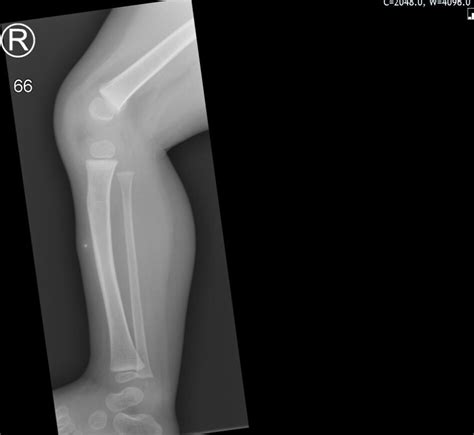

• Imaging Tests: An X-ray is often the first step to determine if the lump is originating from the bone or the soft tissue. Ultrasound, MRI, or CT scans provide more detailed views of the soft tissues surrounding the area.